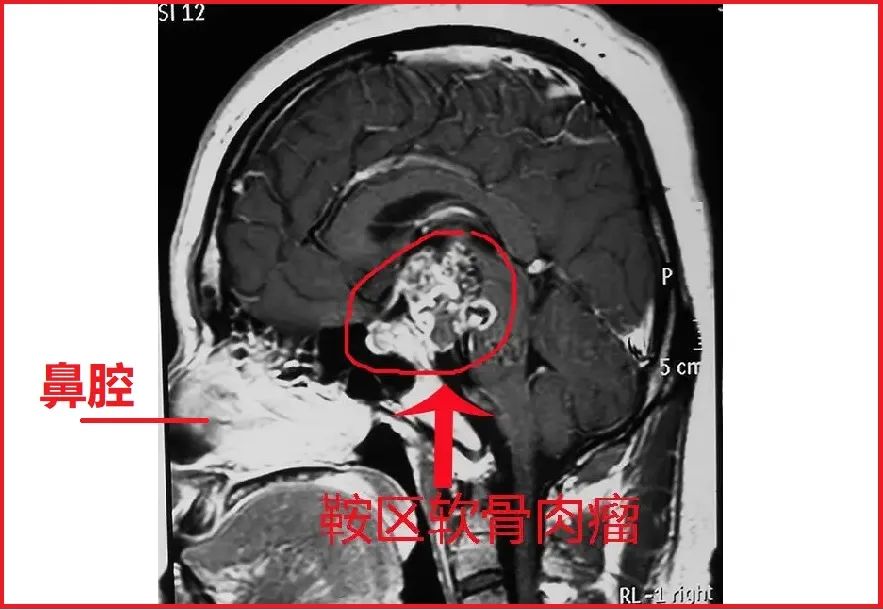

关键就在于,病人是做过鞍区肿瘤手术的。刚刚我们讲了,鞍区是颅内的一个区域,鞍区长了肿瘤(比如垂体腺瘤或者鞍区脑膜瘤等),比如这样的(图片来源网络,非本病人所有):

鞍区肿瘤手术,很多是可以通过鼻腔-蝶窦入路手术切除的。为什么要经过鼻腔进入大脑呢?为什么不直接开颅呢?看这个图大家就明白了:

很明显了,病人由于鞍区长了肿瘤(具体不详),通过鼻腔进入颅底做了手术。术后才放的鼻胃管。